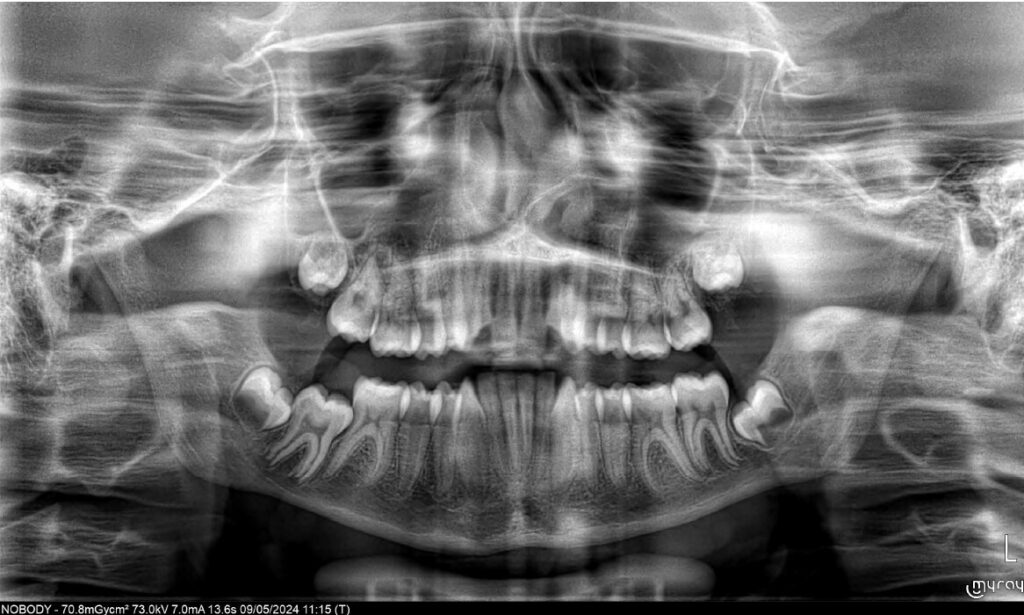

Um paciente do sexo masculino, com 13 anos de idade, apresentou-se com uma mordida profunda, caracterizada pela cobertura quase completa dos incisivos mandibulares. A avaliação clínica revelou apinhamento em ambas as arcadas, rotações dentárias e proclinação dos incisivos laterais superiores, contribuindo para as preocupações estéticas do paciente. O perfil facial era retrusivo, consistente com retrognatismo mandibular, e não foram detectadas anomalias periodontais significativas.

DIAGNÓSTICO:

O paciente apresentava uma relação esquelética de Classe II com molares e caninos bilaterais em Classe II e um padrão dentário de Classe II divisão 2. A mordida profunda estava associada a um apinhamento anteroinferior e a uma curva de Spee acentuada. A análise facial revelou boa simetria, um terço facial inferior ligeiramente aumentado e um perfil convexo caracterizado por retrusão mandibular e do mento. A competência labial estava ligeiramente reduzida, com diminuição do ângulo nasolabial e leve tensão do músculo mentoniano, fatores que comprometiam a harmonia facial global.